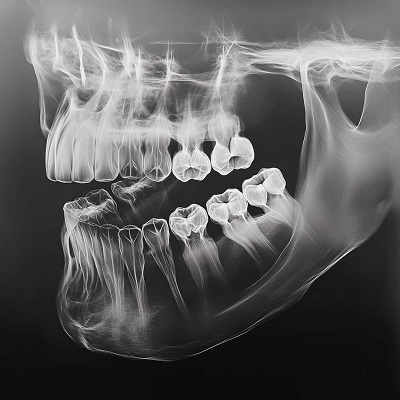

A dental X-ray (also called a radiograph) is a diagnostic image that uses low levels of radiation to create pictures of the interior of your teeth, gums, and jawbones. These images allow your dentist to see hidden structures and conditions that aren’t visible during a standard visual exam, providing a complete view of your oral health.

X-rays can reveal decay developing between teeth and under existing fillings, areas that are impossible to see with the naked eye. Early detection allows for simpler and more conservative treatment.

They provide a clear view of the roots of your teeth and the surrounding jawbone. This is essential for diagnosing infections, abscesses, bone loss due to gum disease, or other abnormalities affecting the tooth’s foundation.

X-rays show the level of the bone that supports your teeth. Dentists use them to diagnose advanced periodontal (gum) disease and monitor its progression over time.

X-rays reveal the position, angle, and development of wisdom teeth. This information is crucial to determine if they are impacted (unable to erupt normally) and need to be removed to prevent pain, infection, or damage to adjacent teeth.

They are indispensable for planning major treatments such as dental implants, root canals, orthodontic braces (like Invisalign), and placing crowns or bridges. X-rays ensure these procedures are planned with precision for a successful outcome.